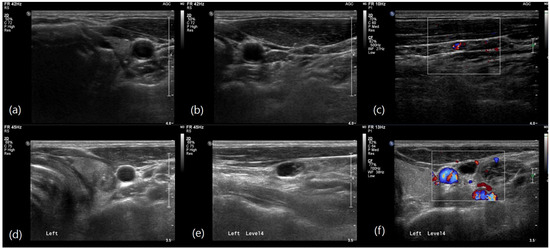

Figure 2. Ultrasound images in N1b papillary thyroid carcinoma. (a) Preoperative ultrasound image of a 55-year-old man showing a 0.6-cm, taller-than-wide hypoechoic cancer with microcalcifications in the left upper portion of the thyroid. (b,c) A 0.5-cm hyperechoic lymph node with increased vascularity is shown on the left side of the neck level III. The final pathology after neck dissection revealed seven metastatic lymph nodes involving level II, III, and IV. (d) Preoperative ultrasound image of a 41-year-old man showing a 1-cm, hypoechoic cancer with microcalcifications in the left upper portion of the thyroid. (e,f) A 1-cm metastatic lymph node with cystic change and peripheral vascularity is shown on the left side of the neck at level IV. The final pathology after neck dissection revealed two metastatic lymph nodes at level IV without level II lymph node involvement.

Multivariable logistic regression analysis identified several independent predictors of level II LN metastasis. In the preoperative model (Table 3), larger tumor size (OR, 1.031; 95% CI: 1.011–1.051; p = 0.002) and nonparallel tumor shape (OR, 1.963; 95% CI: 1.322–2.915; p = 0.001) were significantly associated with level II metastasis. Additionally, the involvement of multiple LN levels and level III were strong predictors with odds ratios of 1.906 (95% CI: 1.242–2.925; p = 0.003) and 1.867 (95% CI: 1.223–2.850; p = 0.004) respectively. In the postoperative model (Table 4), non-conventional pathology was a significant predictor (OR, 1.951; 95% CI: 1.121–3.396; p = 0.018). The presence of extrathyroidal extension (OR, 1.867; 95% CI: 1.060–3.331; p = 0.031) and a higher LN ratio (OR, 1.057; 95% CI: 1.039–1.076; p < 0.001) were also significantly associated with level II metastasis. These findings highlight the importance of comprehensive preoperative evaluation, including a detailed assessment of tumor size, shape, pathology, and LN characteristics, to identify patients at higher risk of level II LN metastasis (Figure 2 and Figure 3).